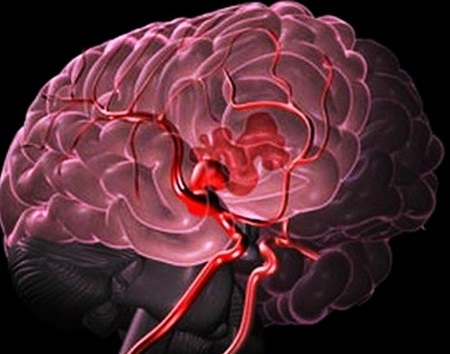

- Аневризма сосудов мозга.

- При высоком артериальном давлении происходит разрыв сосуда с истонченными стенками (из-за развития какого-то заболевания). В результате этого кровь начинает проникать в соседние ткани, что приводит к возникновению гематомы внутри мозга. Формирование гематомы происходит мгновенно. При этой разновидности геморрагического инсульта кровь зачастую прорывается в мозговые желудочки либо субарахноидальное пространство. Из-за чего нарушается венозный отток, начинает формироваться отек, повышается внутричерепное давление. При развитии данных процессов мозг может сместиться, могут быть сдавлены важнейшие структуры, которые регулируют работу дыхательных органов и сердца. Именно поэтому геморрагический инсульт является столь тяжелым заболеванием, которое отмечается низкой выживаемостью.

Геморрагический инсульт – патологический процесс, при котором наблюдается кровоизлияние под оболочки или в вещество головного мозга (не стоит путать с гематологическим инсультом). Кровоизлияние также может наблюдаться в пространство под корой мозга (геморрагический субкортикальный инсульт). Это крайне опасные состояния, при которых существенно нарушается кровообращение в структурах мозга.